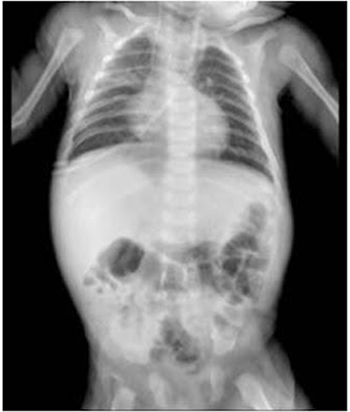

Al día 18 se vuelve a tomar una radiografía de tórax, en la cual destacan radiopacidades en tercio medio de campo pulmonar derecho y retrocardiaca lo cual indica la sospecha de infiltrados pulmonares que pueden ser el resultado de la acumulación de líquido, células inflamatorias o tejido cicatricial en el pulmón. A pesar de ello la evolución clínica es favorable (Figura 3). El día 24, se decidió dar de alta al paciente, ya que había completado el tratamiento indicado. Durante este período, ya no se registraron episodios de fiebre, la presión arterial y la frecuencia cardíaca se mantuvieron estables, y se observó una adecuada perfusión tisular. Además, el hemograma se encontraba dentro de los parámetros normales y el paciente no requería soporte de oxígeno, únicamente se indicó tratamiento para las convulsiones. Se proporcionaron instrucciones de seguimiento adecuadas.